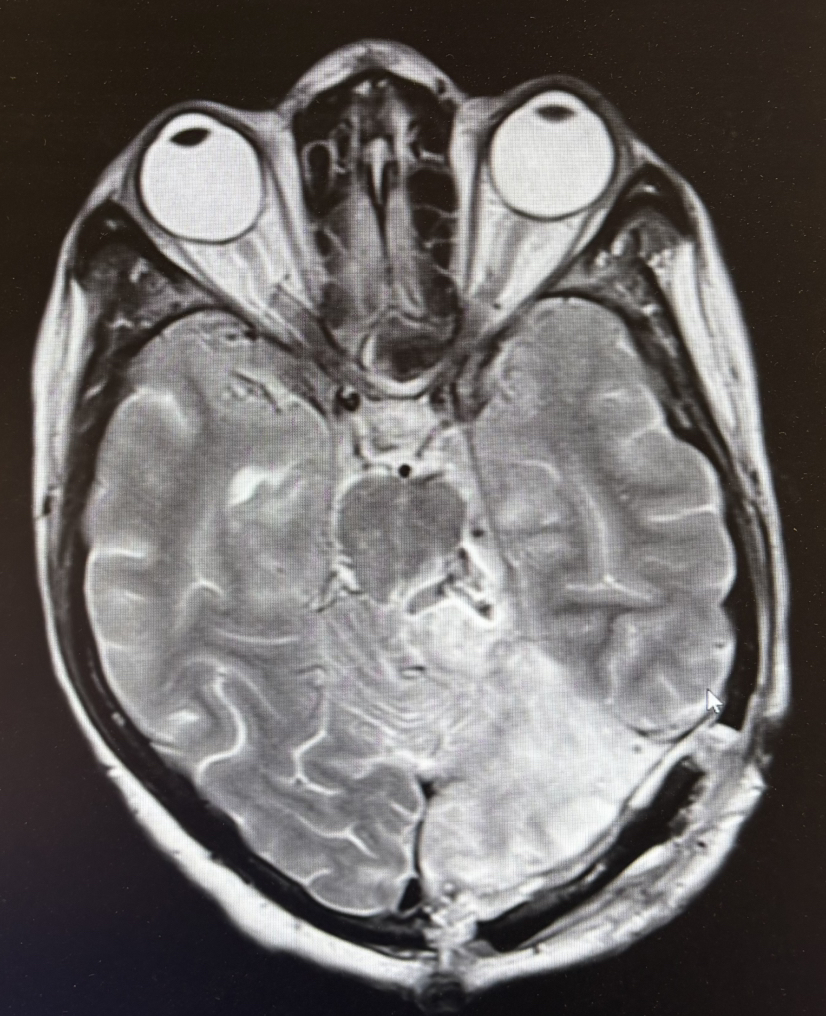

2期术前MRI